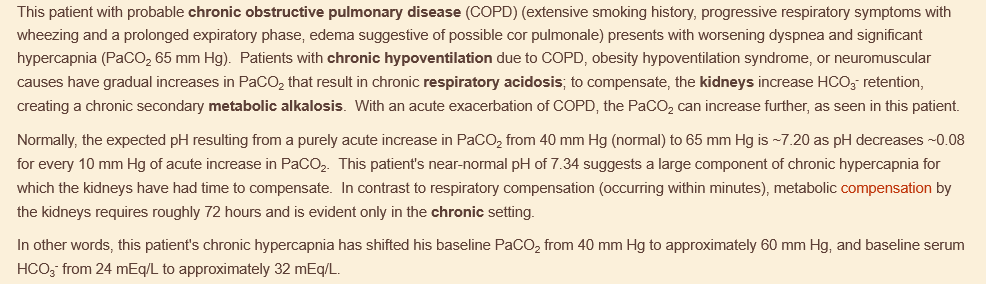

(metabolism) copd leads to….

renal tubular compensation (metabolic alkalosis) to combat respiratory acidosis long-term